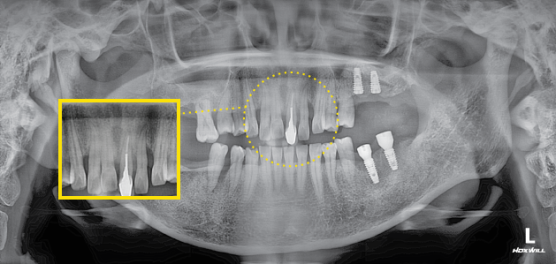

#21.22 정출, #21발치 설명드림. #131211X2223 브릿지 진행

#22 신경노출로 신경치료 진행함.